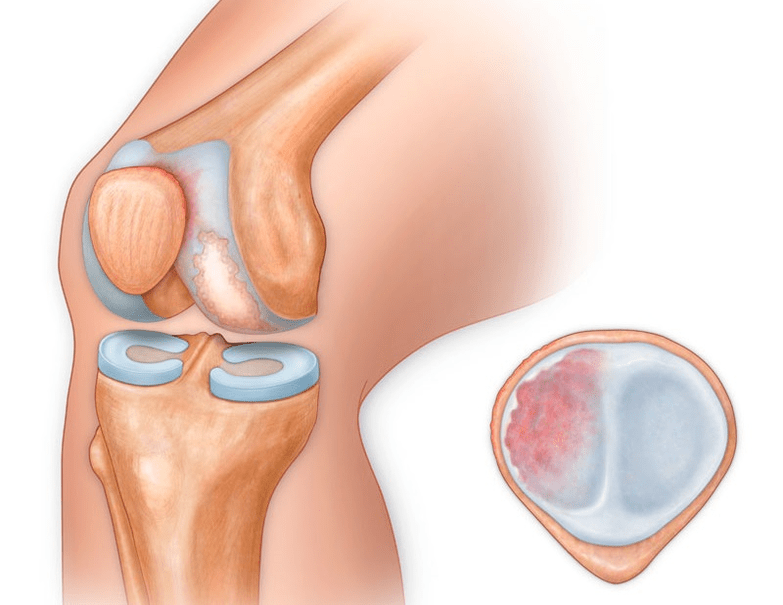

In addition to the inner or outer part of the knee, osteoarthritis can also affect the surfaces between the kneecap and the intercondylar groove of the femur.This option is calledpatellofemoral osteoarthritis.

Its cause is usually a subluxation, fracture or lateralization of the patella.